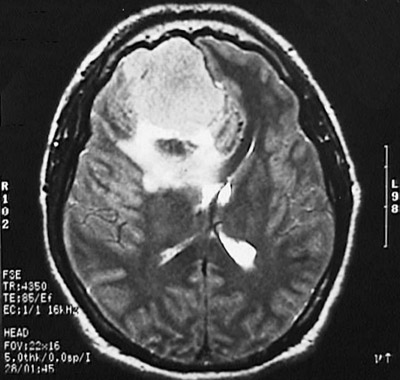

This T2 weighted MRI scan in axial view demonstrates a meningioma in the parasagittal region which is so large that it compresses the underlying cerebral hemisphere and impinges upon the lateral ventricle.